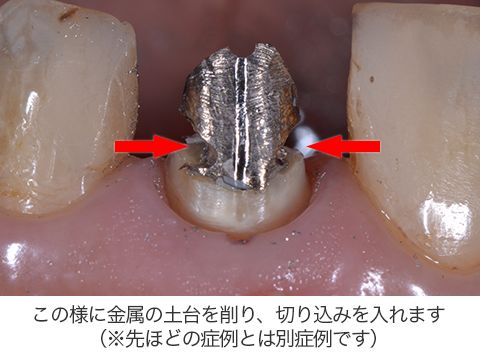

それは「ダブルドライバーテクニック」と言われています。

大阪の根管治療の専門の先生がこの方法を発明しまして、以下の写真の様にマイナスドライバーを2本使ってテコの原理を用い金属の土台を除去します。

このダブルドライバーテクニックでこの先生は脚光を浴びました。

画期的なテクニックをと言えると思います!

80%以上この方法で金属の土台は除去することが可能です。